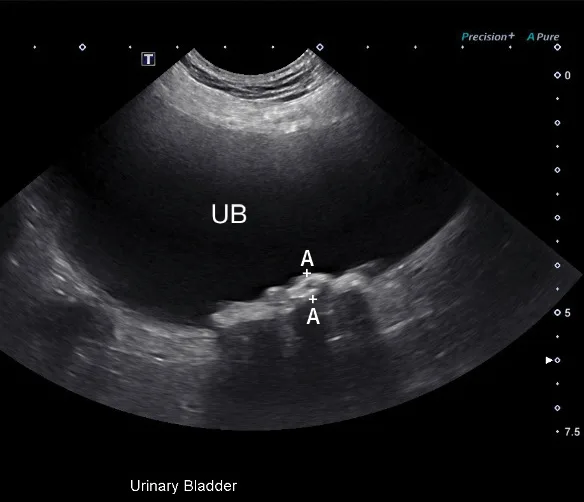

3. Abdominal Mass Identification in the Liver & Spleen

Hepatic and splenic nodules or masses can be primary or metastatic; can be benign or malignant; and may appear as a single mass, multiple masses, or diffusely infiltrative.10,11 Operator skill level, resolution of the ultrasound transducer, and echogenicity of the surrounding parenchyma can impact detection of soft-tissue nodules.12 Common malignant hepatic and splenic neoplasms include hepatocellular carcinoma, hemangiosarcoma, lymphoma, and histiocytic sarcoma. Common benign changes in the liver and spleen include hyperplasia, myelolipoma, hematoma, lymphoid hyperplasia, and extramedullary hematopoiesis.12,13 A large hepatic mass and peritoneal effusion are more often associated with neoplasia than a benign growth in the liver.13 In the spleen, nodules 1 to 2 cm in diameter, multiple targetoid lesions (hyperechoic center with hypoechoic rim), and peritoneal effusion are associated with neoplasia.14 Hepatic and splenic masses can have diverse characteristics, including well- or poorly circumscribed margins, variable echogenicity, fluid cavitation, and mineralization (Figure 3).

FIGURE 3

Transverse image of the right liver in a dog with a hyperechoic and multicavitary liver mass (A; asterisk) adjacent to a normal portion of liver (arrow). Deep (ie, bottom of the image) to the liver and the mass, the diaphragm appears as a hyperechoic line. Hypoechoic mass (B; asterisk) protruding from the splenic capsule.